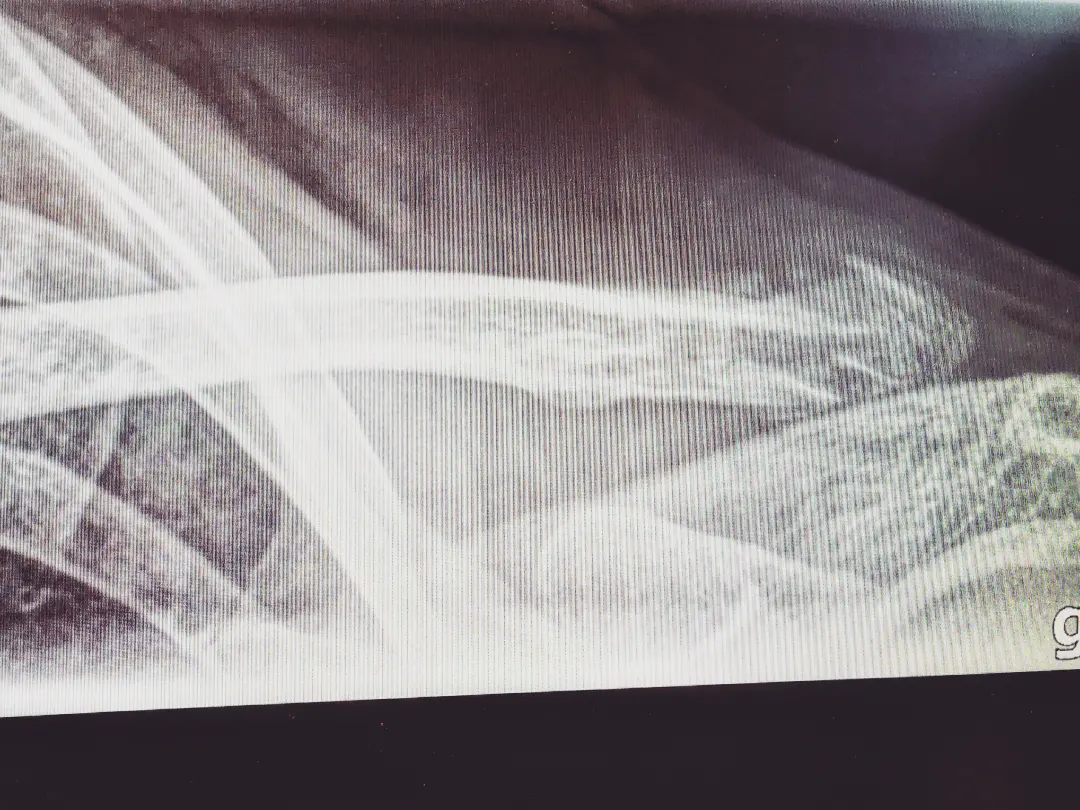

Und im selben Moment, da am Boden, wusste ich gleich Bescheid. Ich brauchte dieses Röntgenbild nicht, um zu wissen, dass bei diesem Sturz heute früh, kurz nach Sonnenaufgang, ein erneuter Knochenbruch mein Wegbegleiter geworden ist.

Injured – once again.

One step. One crack. Und acht Monate nach der letzten OP geht die Reise jetzt wieder mal aufs Neue & von vorne los.